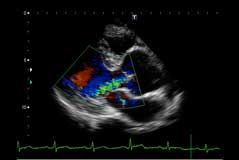

超音波検査(エコー検査)

超音波検査で心臓の動きや機能を観察します。心筋梗塞や心臓弁膜症など心不全の評価に非常に有効です。

心臓の形の異常を発見する形態的診断や、心臓の働きや機能を見る機能的診断があり、総合的に心臓を評価します。心臓は常に拍動していますが、動いている状態をそのまま観察出来る、とても有用な検査です。脳梗塞などの原因となる不整脈に伴う心房内血栓の発見などにも、非常に有効です。